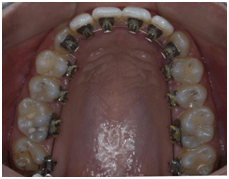

The orthodontist will assess the teeth that need to be aligned and create either a fixed or removable brace, which can be adjusted during the course of the treatment to achieve the desired effect. The fixed braces, as their name implies, are permanent fixtures and are removed at the end of the treatment period, whereas removable braces can be taken off for eating and cleaning but are generally worn at all other times. Braces will improve the function of the teeth and the general appearance of the person.

Misplaced/Maligned teeth or an “improper bite” can not only detract from people’s smiles; but may also lead to tooth decay, gum disease and eventual early tooth loss. For these, among other reasons everyone should have an orthodontic check-up at least once, the ideal age for which would be 7-15 years, though age is not a bar for treatment with braces. At Precision Dental Care we complete the treatment in minimum time period i.e. 8-12 months.